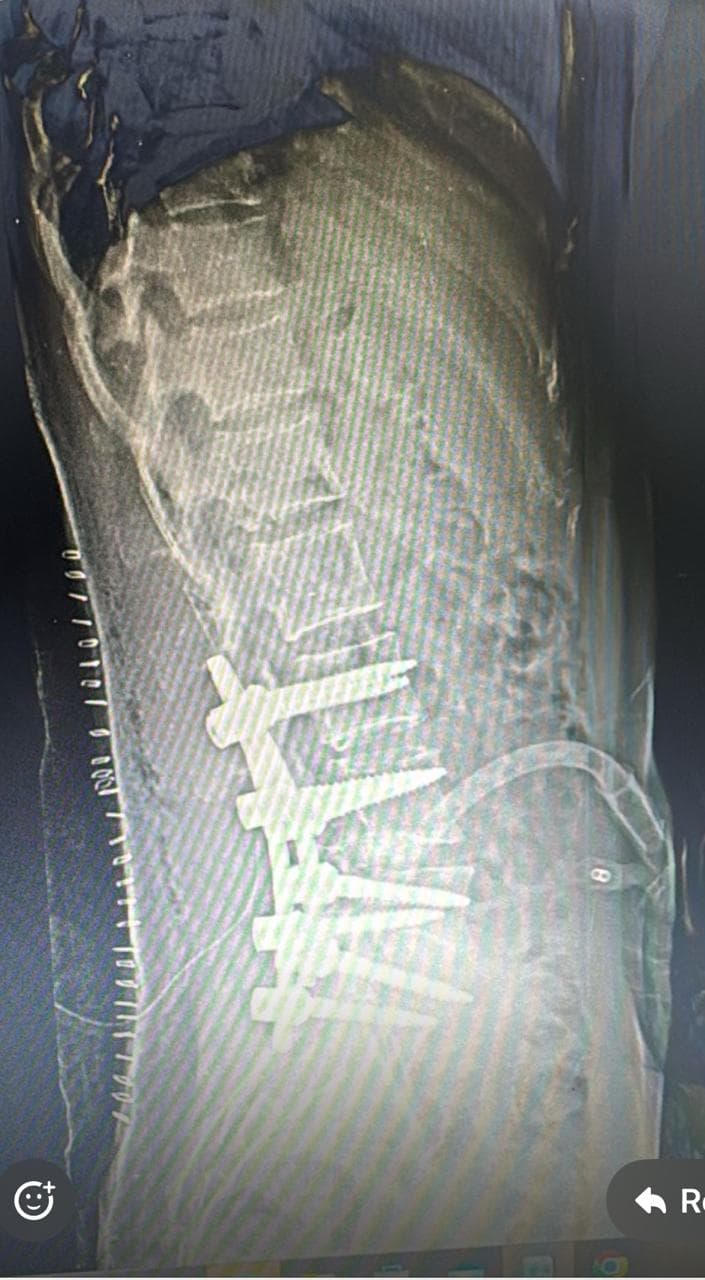

In this patient’s case, the hemivertebra at L4 created a significant lumbosacral curve that affected the natural biomechanics of the spine, causing pain, a tilted posture, and aesthetic concerns.

After thorough evaluation and counseling, Dr. Bhupendra Pratap Bharti , a leading spine deformity correction specialist, recommended surgical correction to prevent further progression of the curve and relieve her symptoms.

The chosen surgical approach was:

This approach was chosen for its effectiveness in correcting deformity while preserving spinal mobility, especially important in a young and active patient.

The surgery was performed with high precision under intraoperative neuromonitoring to ensure spinal cord safety. Post-operatively, the patient: